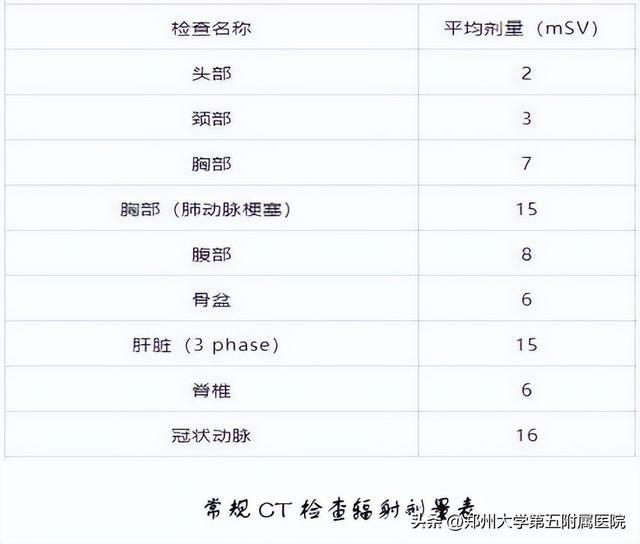

02CT (電子計算機體層攝影)

用X射線束對人體某部位一定厚度地掃描,根據人體不同組織對X線的吸收與透過率的不同,應用靈敏度極高的儀器對人體進行測量,然後將測量所獲取的數據輸入電子計算機,電子計算機對數據進行處理後,就可獲取人體被檢查部位的斷面或立體的圖像,發現體內任何部位的細小病變。它是通過數據計算得到的重建圖像。

雖然CT依舊用的是X射線,但不同於X光用的是X射線的螢光作用直接在攝影膠片或螢屏成像,CT則是通過數據計算得到的重建圖像。X線與CT檢查均有輻射!

我們每個人每天都在接受來自宇宙射線和自然界天然放射性核素髮出的電離輻射,稱本底輻射。因各地地表放射性物質含量不同,劑量約2.4~6.0mSv/年。目前研究表明,本底輻射水平對人體健康沒有影響。

根據《電離輻射防護與輻射源安全基本標準GB18871-2002》人體可接受的年輻射劑量限值為50mSv。